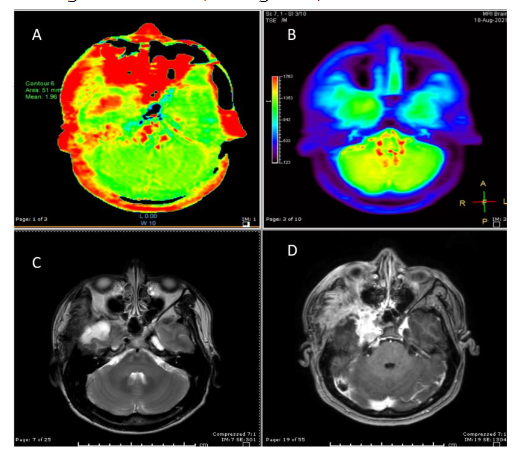

Figure 5: Meningioma, Chordoid variant (WHO grade II): APT mean and APT max = 4.38, ADC value = 0.77 and ADC ratio = 1.09 (A) APT-weighted image shows increased APT signal at the right parietal convexity mass, note ROIs were placed at the highest APT signal area corresponding to the S0 image (C) (B) T2-weighted image and (E) contrast-enhanced T1-weighted image show enhancing mass at the right pareital convexity in keeping with meningioma (D) ADC maps with ROIs placed at the meningioma (F) SWI shows no internal calcification or hemorrhage.